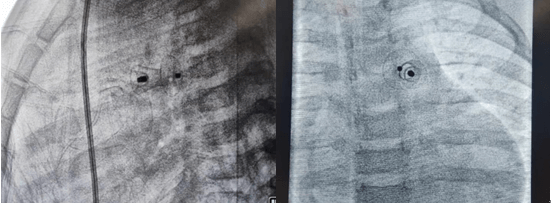

2021年11月12日,延安大學(xué)咸陽(yáng)醫(yī)院心血管病院吳棟梁院長(zhǎng)、李陽(yáng)主任介入團(tuán)隊(duì)為一例年僅13個(gè)月的女性患兒進(jìn)行了先天性心臟病動(dòng)脈導(dǎo)管未閉介入封堵手術(shù)。這是我院迄今為止介入封堵治療年齡最小、體重最輕的患兒,手術(shù)過程順利,封堵成功,解決了一家人的痛苦,患兒術(shù)后恢復(fù)良好,于2021年11月17日順利出院。

先天性心臟病發(fā)病率已逐年下降,但因我國(guó)人群基數(shù)大,所以患者并不少見,先天性心臟病也是心血管疾病中為數(shù)不多的可通過介入或者外科手術(shù)得到根治的疾病之一,一般手術(shù)多建議在3歲以后進(jìn)行,3歲以內(nèi)患兒因體重太小,對(duì)患兒進(jìn)行動(dòng)靜脈穿刺置管、手術(shù)操作過程及麻醉難度明顯增加。該患兒體重僅10kg,身高僅70cm多一點(diǎn),因動(dòng)脈導(dǎo)管分流量較大,影響患兒發(fā)育,反復(fù)因肺部感染誘發(fā)心衰,并已經(jīng)出現(xiàn)左房左室擴(kuò)大,需盡早手術(shù),否則出現(xiàn)心衰加重可能錯(cuò)過手術(shù)時(shí)機(jī),但患兒家屬對(duì)外科開胸心存畏懼,而且外科手術(shù)后胸部手術(shù)瘢痕明顯影響女性患者的美觀,通過多方打聽,患兒聯(lián)系到了何克強(qiáng)醫(yī)生、李陽(yáng)主任及吳棟梁院長(zhǎng)手術(shù)團(tuán)隊(duì),家屬對(duì)醫(yī)生期望值極高,因患兒情況特殊,吳棟梁院長(zhǎng)及心血管內(nèi)科五病區(qū)團(tuán)隊(duì)術(shù)前對(duì)患兒手術(shù)情況進(jìn)行討論,制定嚴(yán)密的手術(shù)方案,對(duì)手術(shù)中可能出現(xiàn)的難點(diǎn)進(jìn)行充分的準(zhǔn)備,最終在穿刺及麻醉成功后1小時(shí)內(nèi)便順利完成手術(shù),此例手術(shù)的開展,標(biāo)志著我院在先心病介入治療方面再上新臺(tái)階,患兒術(shù)后恢復(fù)非常好,得到了患兒家屬的肯定,解決了患兒一家的困擾。